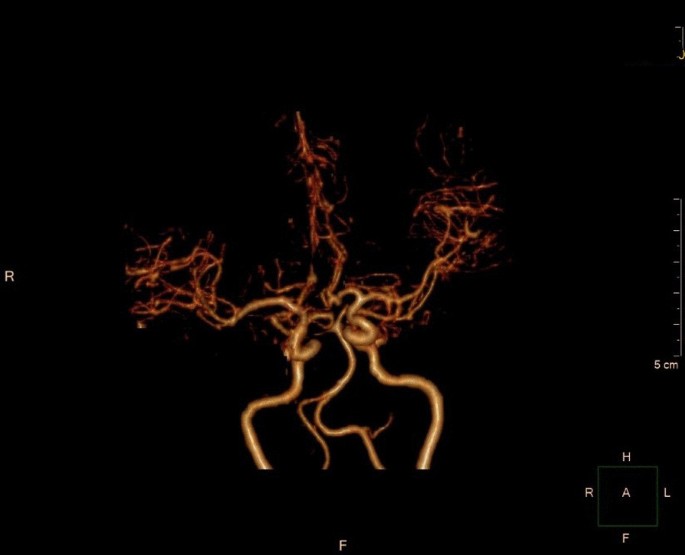

General anesthesia was induced and maintained according to standard protocols during surgical preparation. Then right pneumonectomy was performed, and the surgical incision was located at the posterolateral side of the fourth intercostal space. The pulmonary artery, pulmonary vein and bronchus were cut off with a stapler, with intraoperative bleeding of about 100 ml. After the operation, the thoracic drainage tube was clamped, and the patient returned to the ward after waking up. Three hours after the operation was completed, the patient suddenly lost consciousness while sitting in bed chatting with his wife. The patient’s blood pressure was low (76/53 mmHg), and the indexes of heart rate, respiration and oxygen saturation were normal. After opening the thoracic drainage tube, a small amount of tension gas and 200 ml of bloody fluid was discharged. We immediately performed CT examination and excluded brain lesions. CT examination showed that there was a large amount of gas in the tissue space between the chest and neck (Fig. 2). Blood clots accumulated in the thoracic cavity, and CT angiography showed no abnormalities in the major cerebral arteries (Fig. 3). However, multiple free air can be seen in the blood vessels of bilateral frontal sulcus (Fig. 4). In addition to free air, suspicious cerebral infarction was also seen in the right occipital lobe (Fig. 5). It is presumed that air entering the cerebral circulation led to air embolism. The patient had seizures soon after the CT scan, manifesting as binocular gaze and tremor of limbs. Then the patient was quickly transferred to ICU. Respiratory assistance, mannitol dehydration and empiric antibiotic treatment were used after ICU transfer. 800 ml pleural fluid was drained from the thoracic cavity 6 h after the operation, and a second thoracotomy was performed to stop bleeding. Then blood clot was removed from the thoracic cavity. After the operation, the patient was sent back to the ICU for ventilator-assisted breathing, and the head was protected by mild hypothermia using an ice blanket to prevent excessive brain damage. At the same time, mannitol dehydration was used to reduce brain edema and anti-infection treatment was carried out. On the next day, the brain CT showed a significant decrease of air in the brain (Fig. 6). There was no significant increase in cerebral infarction lesions compared with the first day. After 3 days of ventilator-assisted breathing, the patient’s condition gradually improved. On the third day after air embolism, the brain CT was reexamined. There were patchy low density areas in bilateral thalamic basal ganglia, temporal lobe and occipital lobe, which was cerebral infarction lesions. The patient was discharged after 25 days of treatment after cerebral infarction. He was conscious at the time of discharge, with neurological impairment symptoms of bilateral in which symptoms of left limb are more serious. The process from onset to recovery was smooth. After 3 months of follow-up, most of the neurological deficit symptoms had been recovered except for the left upper limb (Fig. 7).